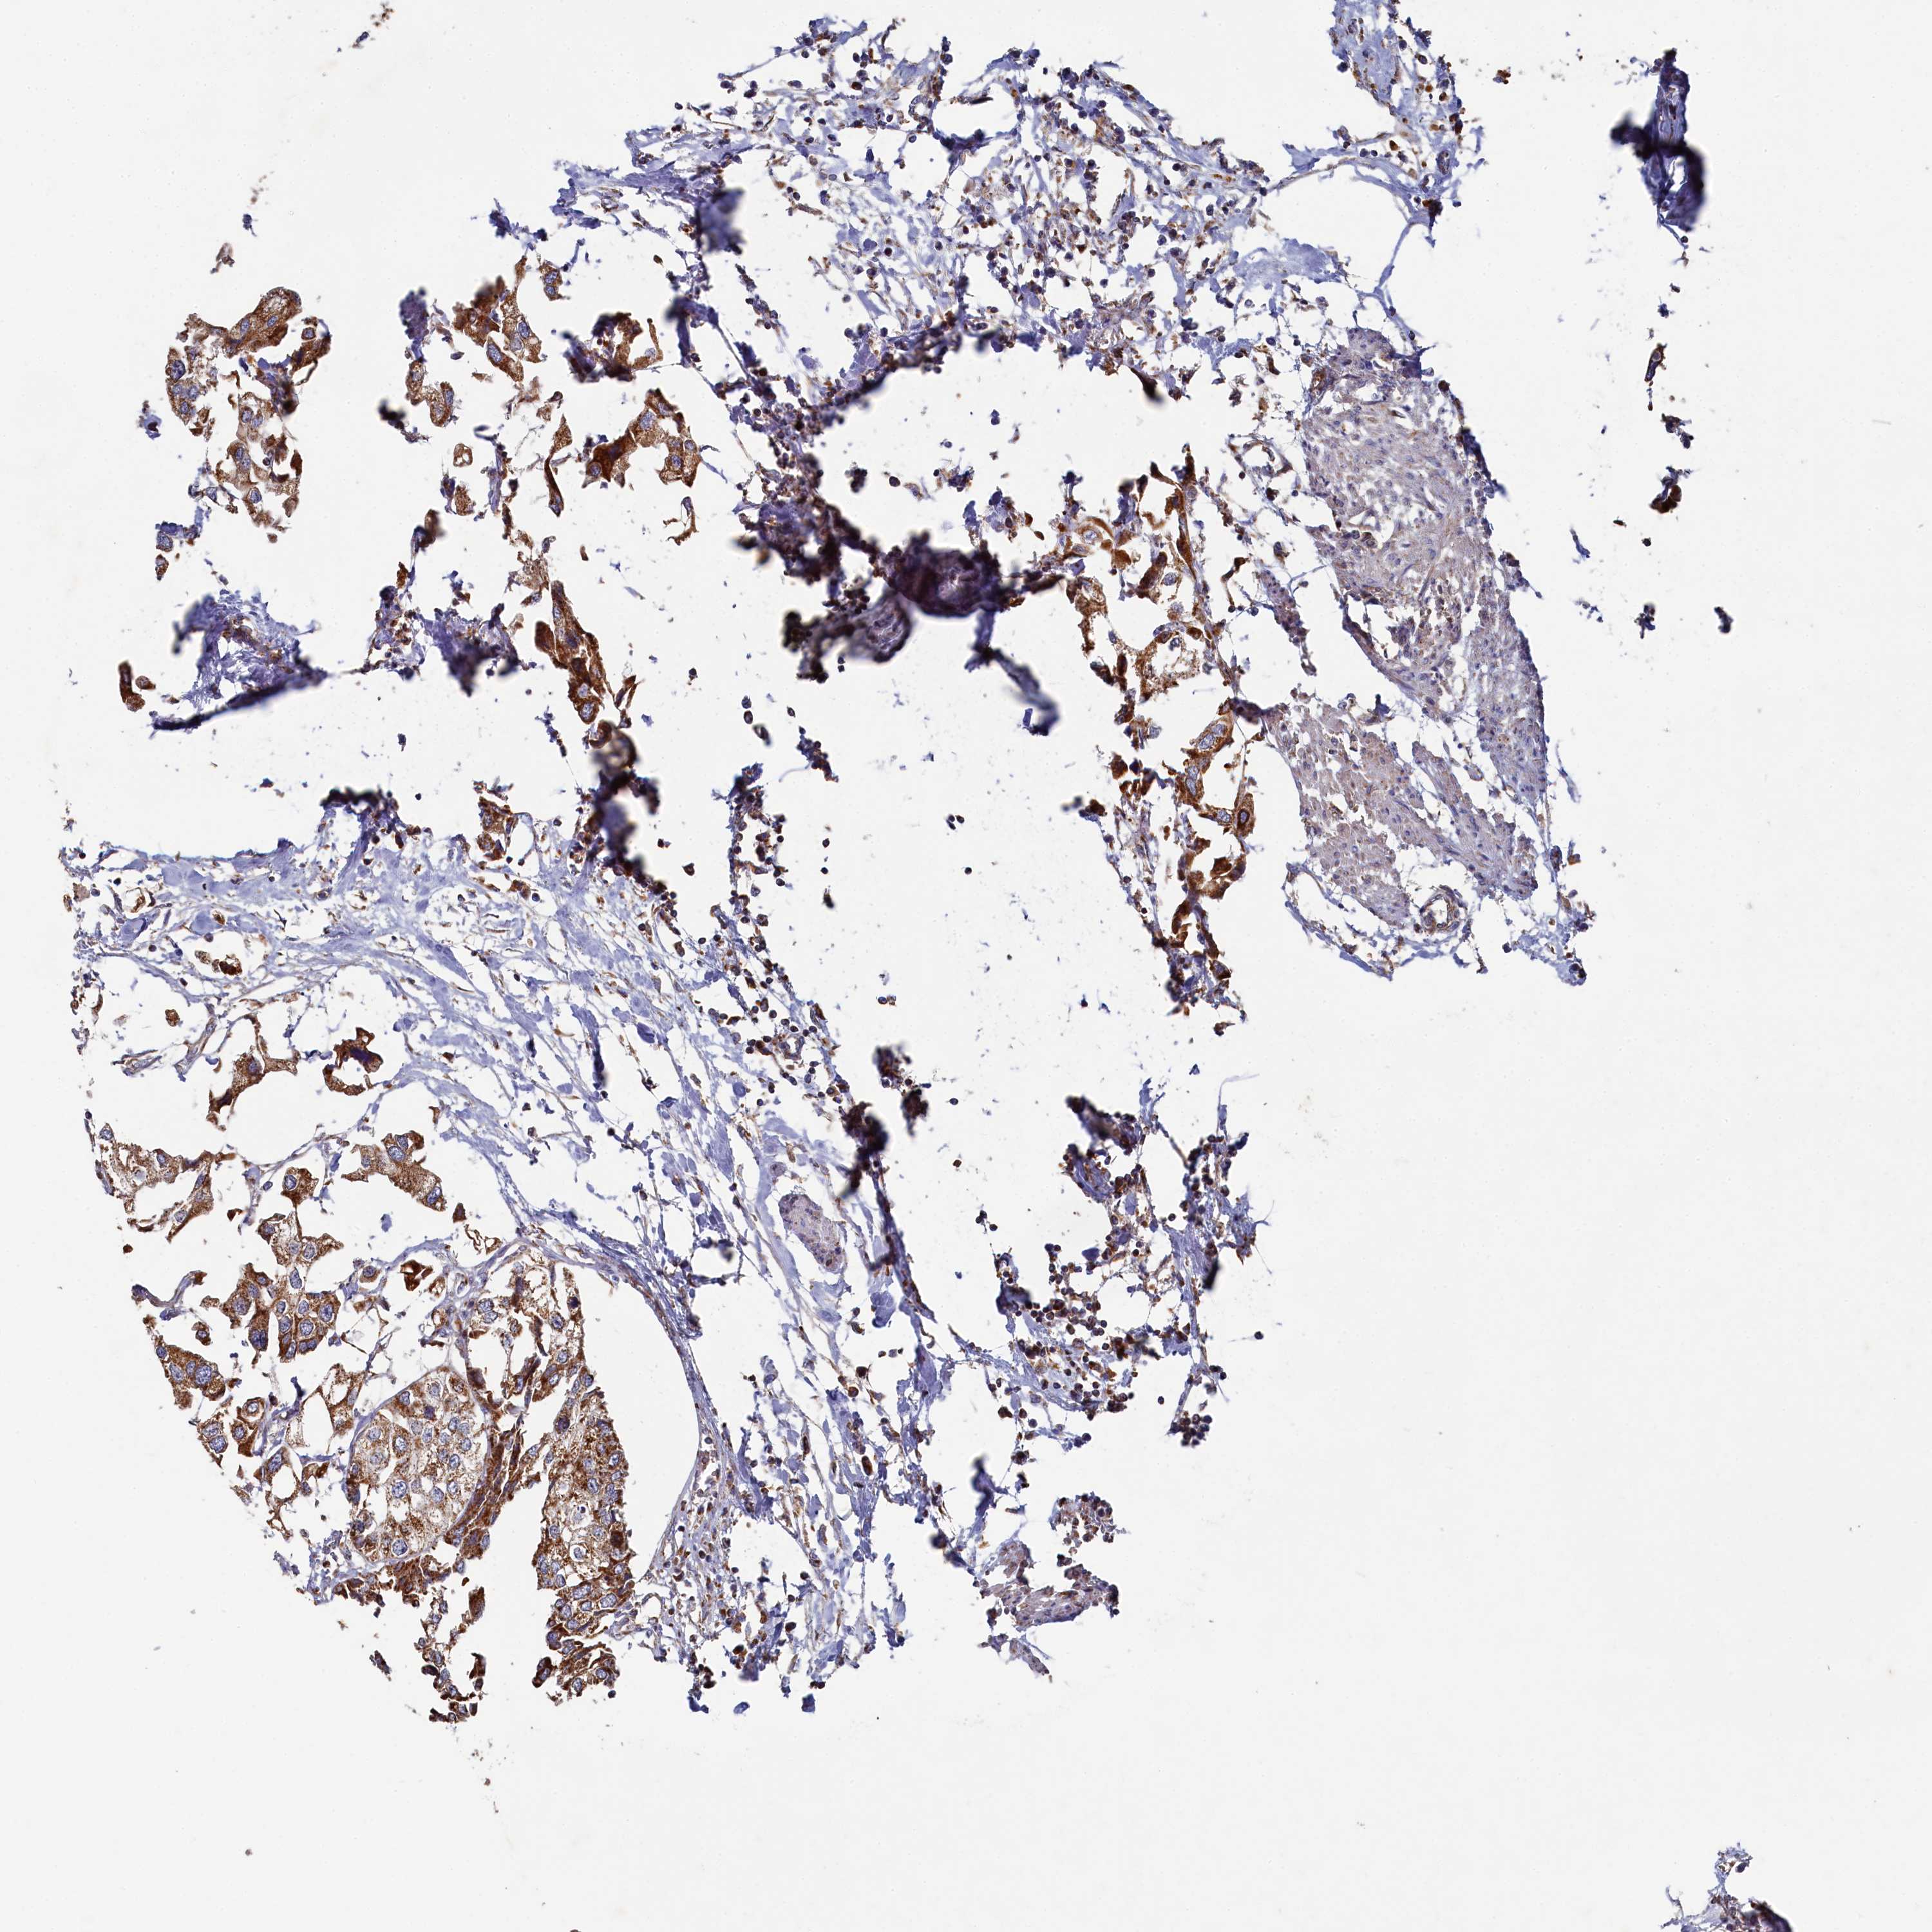

UROTHELIAL CANCER - Protein expressioni

A mouse-over function shows sample information and annotation data. Click on an image to view it in a full screen mode. Samples can be filtered based on level of antibody staining by selecting one or several of the following categories: high, medium, low and not detected. The assay and annotation is described here.

Note that samples used for immunohistochemistry by the Human Protein Atlas do not correspond to samples in the TCGA dataset.

Antibody stainingi

Antibody staining in the annotated cell types in the current human tissue is reported as not detected, low, medium, or high, based on conventional immunohistochemistry profiling in selected tissues. This score is based on the combination of the staining intensity and fraction of stained cells.

Each image is clickable and will lead to virtual microscopy that enables deeper exploration of all samples and also displays staining intensity scores, fraction scores and subcellular localization as well as patient and tissue information for each sample.

Antibody HPA039965

Staining

High

Medium

Low

Not detected

Intensity

Strong

Moderate

Weak

Negative

Quantity

>75%

75%-25%

<25%

None

Location

Nuclear

Cytoplasmic/membranous

Cytoplasmic/membranous,nuclear

Urothelial carcinoma, High grade

Urothelial carcinoma, Low grade